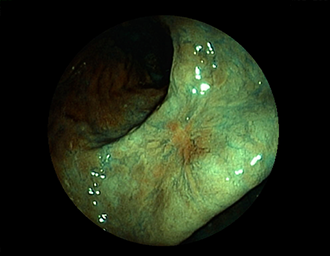

症例1:胃潰瘍(37才、男性)

①胃潰瘍(Stage A1)

健診:胃レントゲン検査で、胃角部ニッシェを指摘され当院受診。

胃角部小弯に、深くて大きな、大きさ約10mmの胃潰瘍(stage 1)

があり、潰瘍底は一部白苔はみ出しを認める。エソメプラゾールマグネシウム水和物投薬で治療開始しました。

(インジゴカルミン散布画像)